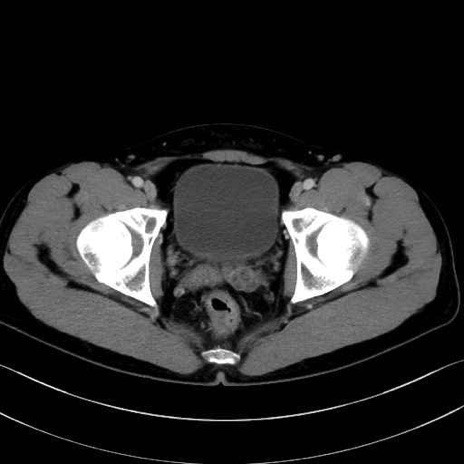

肛門挙筋(levator ani muscle)のCT画像の解剖

肛門挙筋 (Levator ani)